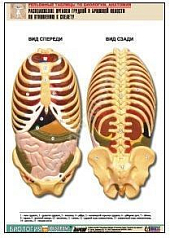

20. Расположение органов грудной и брюшной полостей по отношению к скелету;